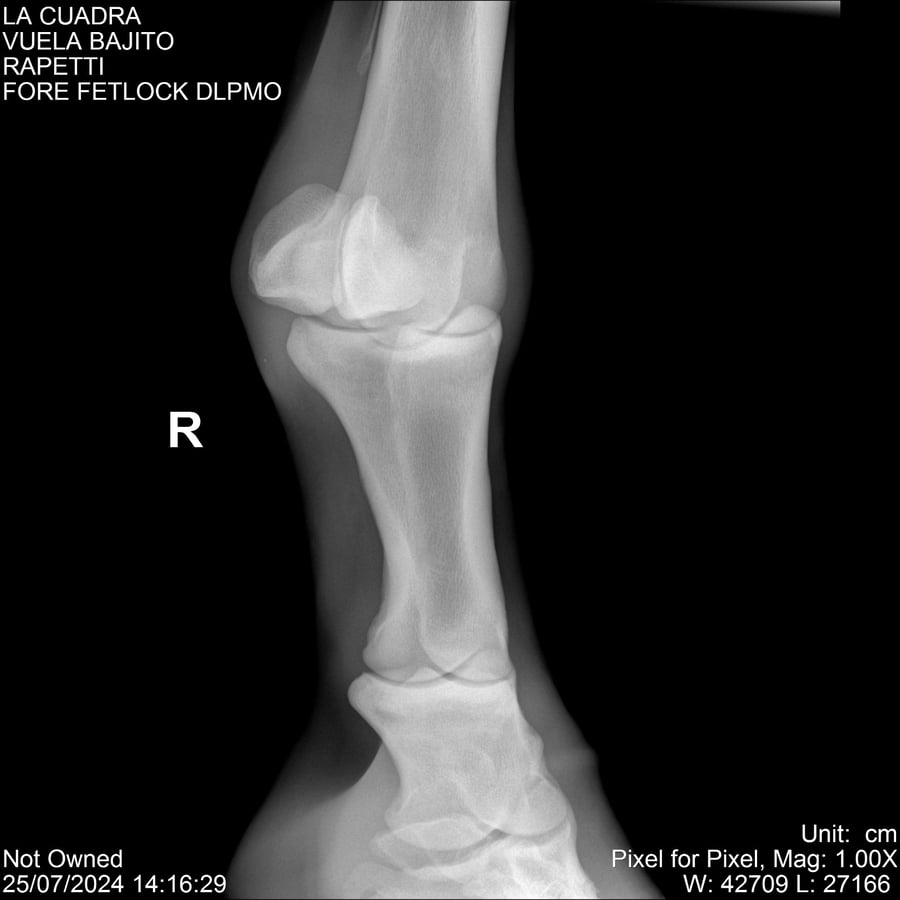

LOTE 16, VUELA BAJITO Lote Anterior Volver al remate Lote Siguiente Ficha Contacto Montevideo - Ficha del Lote Identificador: #284451 Categoría: Yeguarizos Montevideo - 77 Visualizaciones ClicData Contacto Empresa: Abelenda N. R., Walter Hugo Nombre*: Teléfono* : E-mail* : Mensaje Enviar Registrese gratis Este contenido Exclusivo está disponible sólo para usuarios registrados Ingresar